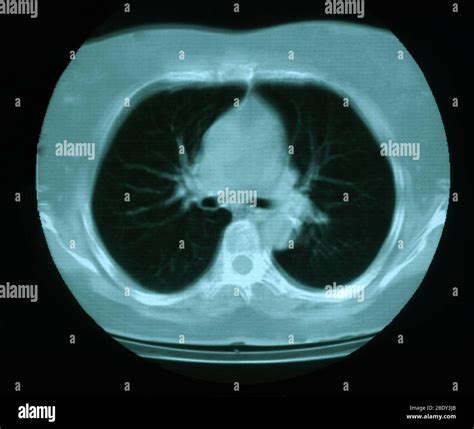

• CT Scan: A computed tomography (CT) scan provides detailed images of the lungs and can help identify the location and extent of the calcification.

Calcification in lungs refers to the abnormal deposition of calcium salts in the lung tissue. This process can affect the lungs' structure and function, leading to various respiratory issues. The calcium deposits can form in different parts of the lung, including the alveoli, bronchi, and blood vessels. The severity and impact of calcification in lungs can vary widely depending on the underlying cause and the extent of the deposits.